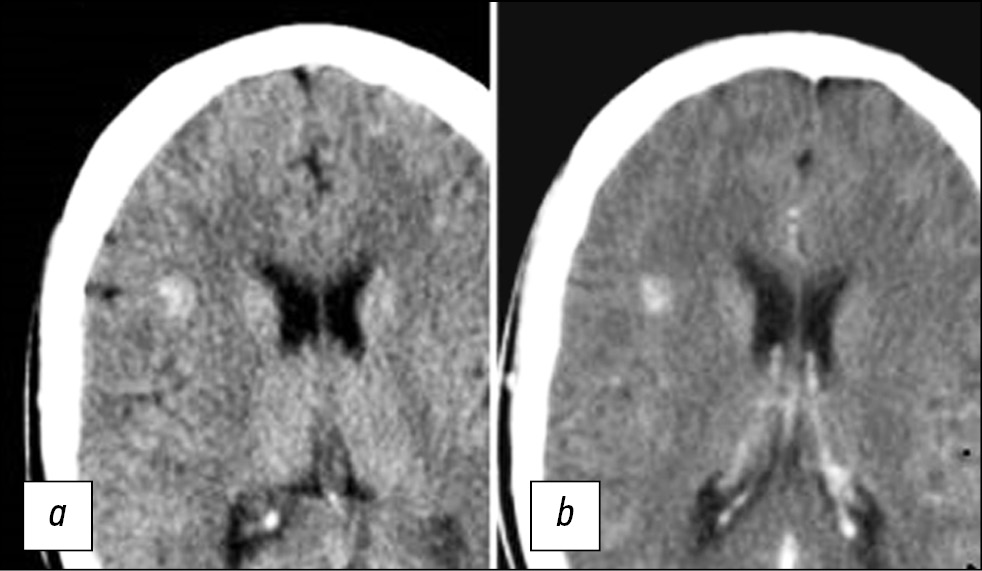

As the only method for detecting CM, CT can be applied to diagnose foci only in 30%–50% of cases. CT images usually show hyperdensive lesions and less often mixed hyper- and isodensive lesions (Fig. 1) [17]. CT can also detect signs of lesion calcification.

Fig. 1. CT sections of the brain in the axial view performed before (a) and after contrast agent administration (b). The images show a hyperdensive focus in the right frontal lobe, without clear contours, and without contrast uptake.

With the introduction of a contrast agent, the definition of CM contours has improved, and sensitivity in detecting isodensive foci has increased. Some researchers [18] suggested the following signs of CM based on CT results: round shape, clearly defined edge, uneven density, absence of surrounding edema, and mass effect (in the absence of intracerebral hemorrhage). However, CT results in the diagnosis of CM are nonspecific. Thus, the differentiation of CM and partially calcified avascular gliomas is a significant problem.